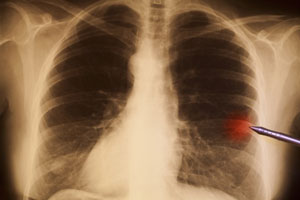

Kaszel jest złożonym objawem występującym w wielu chorobach układu oddechowego, przy czym u chorych na raka płuca może w istotnym stopniu ograniczać jakość życia. Na podstawie obserwacji u zwierząt rozpoczęto badania u ludzi mające na celu ocenę skuteczności leczenia kaszlu poprzez wpływ na czynność neurokinin.